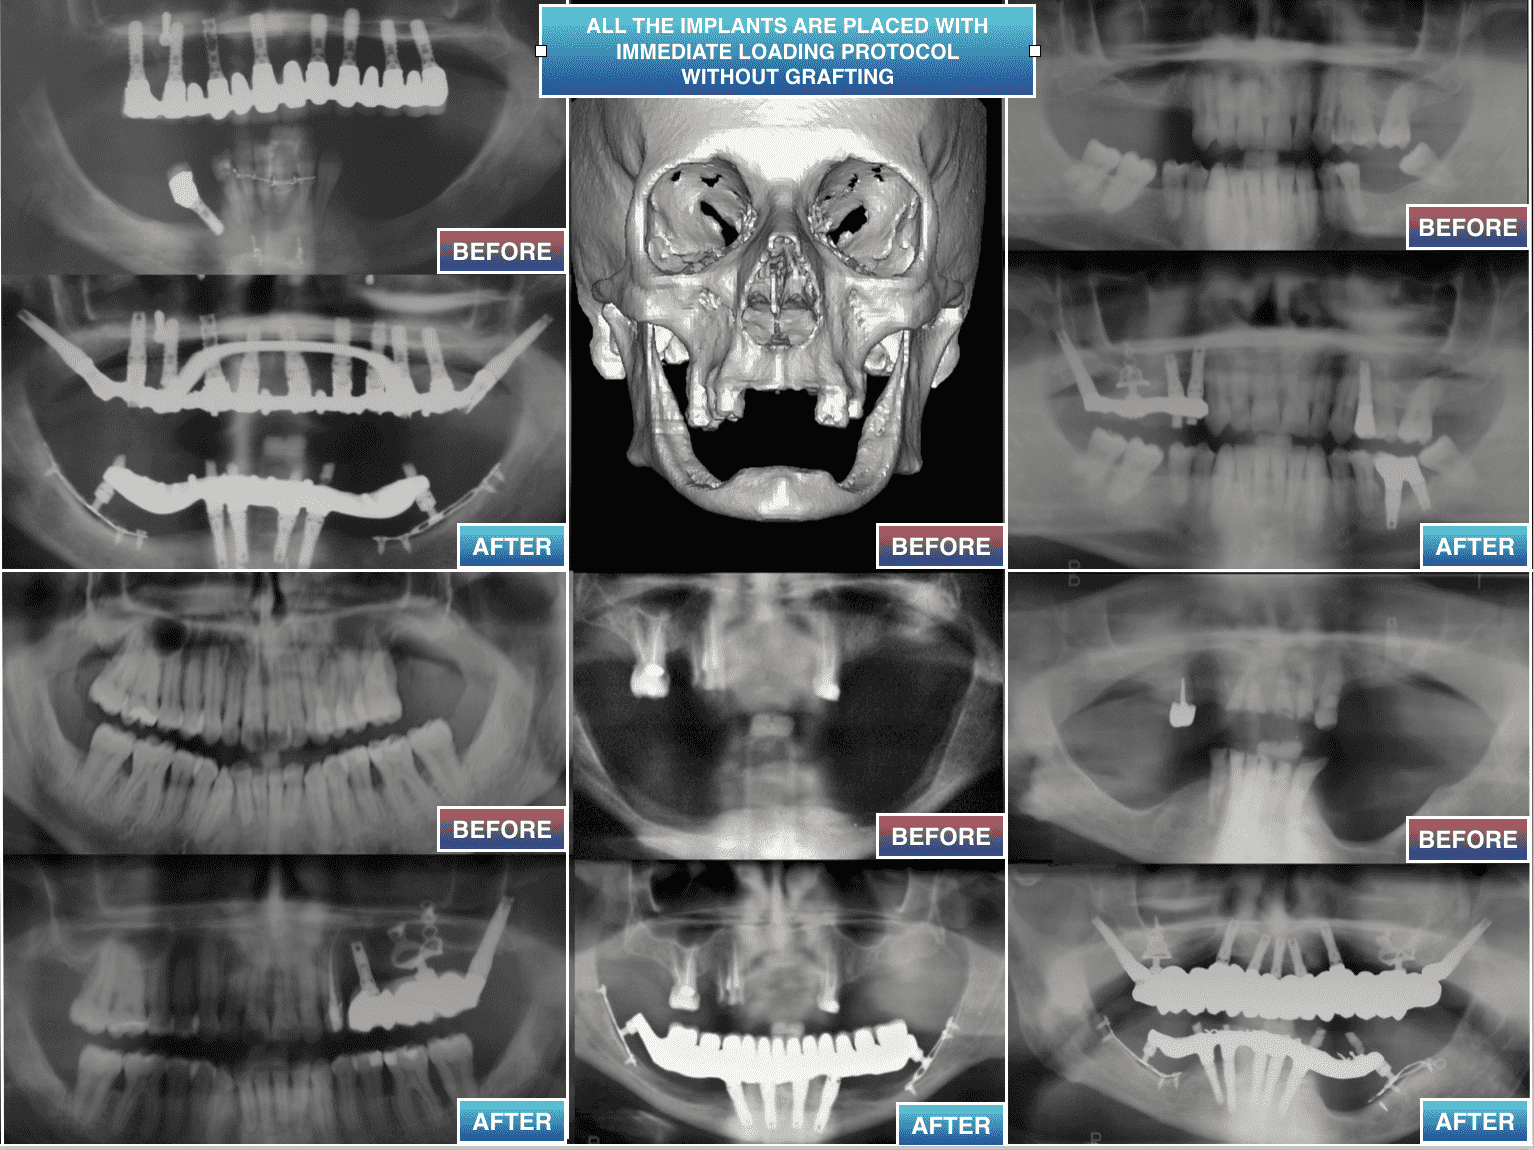

Depuis plus de 30 ans nous pratiquons des procédures de chirurgie en implantologie dentaire sans passer par la greffe,

quand elles ne peuvent être appliquées ou quand elles ont échoué